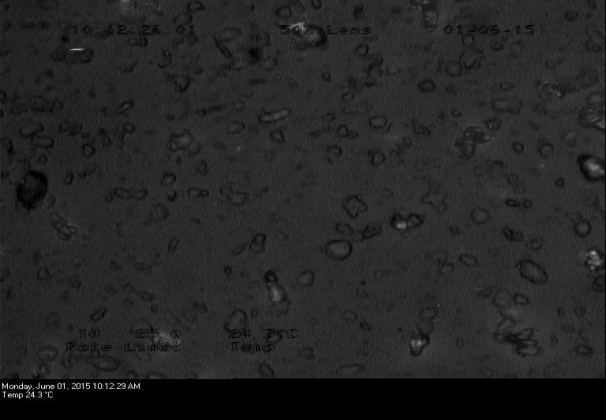

Optical and polarized microscopy

Each sample (<0.1 mg) was mounted on a glass slide with a brush, covered with silicone oil and a coverslip and was observed under the microscope (Lecia DMLP, Germany). Light intensity was adjusted and observations were done under normal and polarized light (by engaging the polarizer). Birefringence patterns were observed at a high-resolution scale and images were acquired.

Fig. 2: Optical micrographs of (a1) FB (b1) Spray-dried FB (c1) HPMC physical mixture (d1) HPMC solid dispersion (e1) HPMCAS physical mixture (f1) HPMCAS solid dispersion. Polarized micrographs of (a2) FB (b2) Spray-dried FB (c2) HPMC physical mixture (d2) HPMC solid dispersion (e2) HPMCAS physical mixture (f2) HPMCAS solid dispersion

Optical and polarized microscopy was done to observe the birefringence pattern. Fig. 2 showed optical and polarized micrographs of the drug, polymeric carriers, physical mixtures and solid dispersions. Presence of birefringence confirms the presence of crystallinity in the samples. However, loss of crystallinity was observed in prepared physical mixtures and solid dispersions by uniform dispersion of the drug in molecular matrix. This phenomenon suggested effective encapsulation of FB into the hydrophilic matrix of HPMC and HPMCAS with no evidence of FB crystals on the surface.